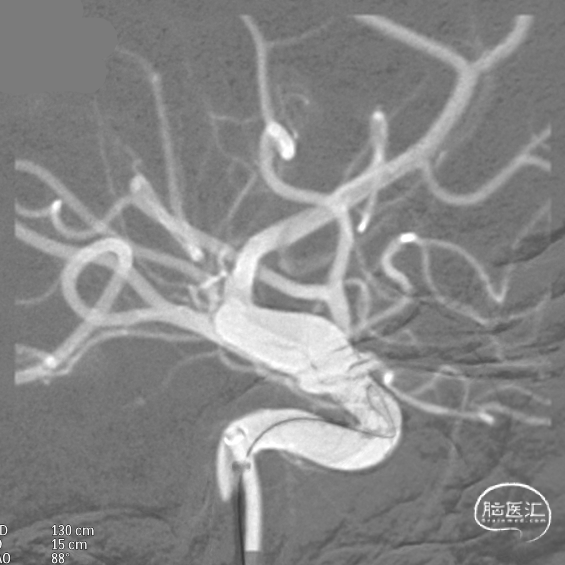

CTA:右侧颈内动脉C6段动脉瘤。

DSA:DSA提示右侧颈内动脉C6段可见多发动脉瘤。

其他血管造影未见明显异常。

术前诊断:右侧颈内动脉C6段多发动脉瘤。

治疗方案:血流导向装置植入术。

载瘤动脉远端血管直径:4.0mm

载瘤动脉近端血管直径:4.9mm、4.5mm(两个角度)

支架到位,远端打开(正侧位):4.75-20mm支架在大脑中动脉M1段打开,回撤至C6段远端锚定。支架释放过程中,轻柔推送支架系统,可见支架导管沿血管壁大弯侧走行,支架打开良好。

术后造影:支架覆盖两枚动脉瘤瘤颈,贴壁良好,瘤体内可见造影剂滞留。

术后支架显影: